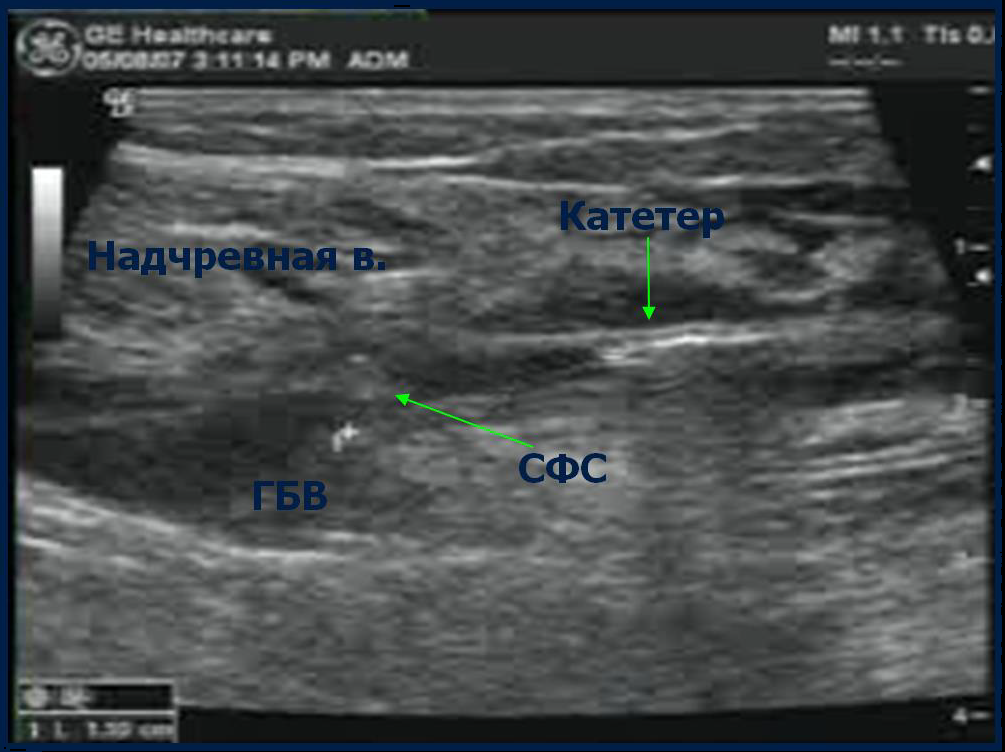

ФИНАЛЬНЫЙ КОНТРОЛЬ ПОЛОЖЕНИЯ КОНЧИКА КАТЕТЕРА

Под контролем УЗИ убедитесь, что кончик катетера расположен на 2 см дистальнее СФС

Оптимальное расположение кончика катетера - на 2 см дистальнее СФС